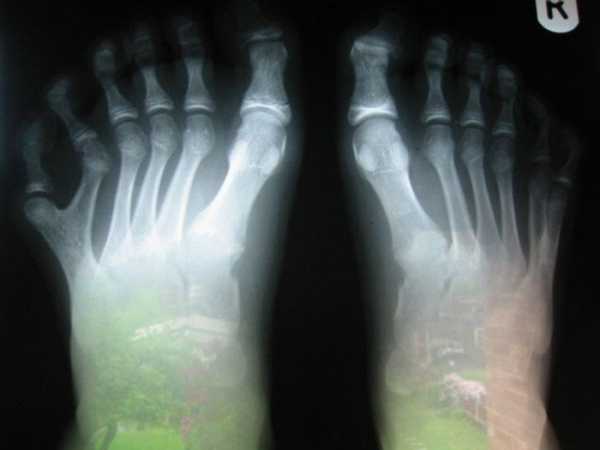

Хлопець народився із 12 пальцями на ногах

Полідактилія